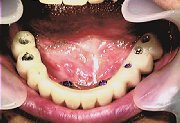

| 症例1 インプラント